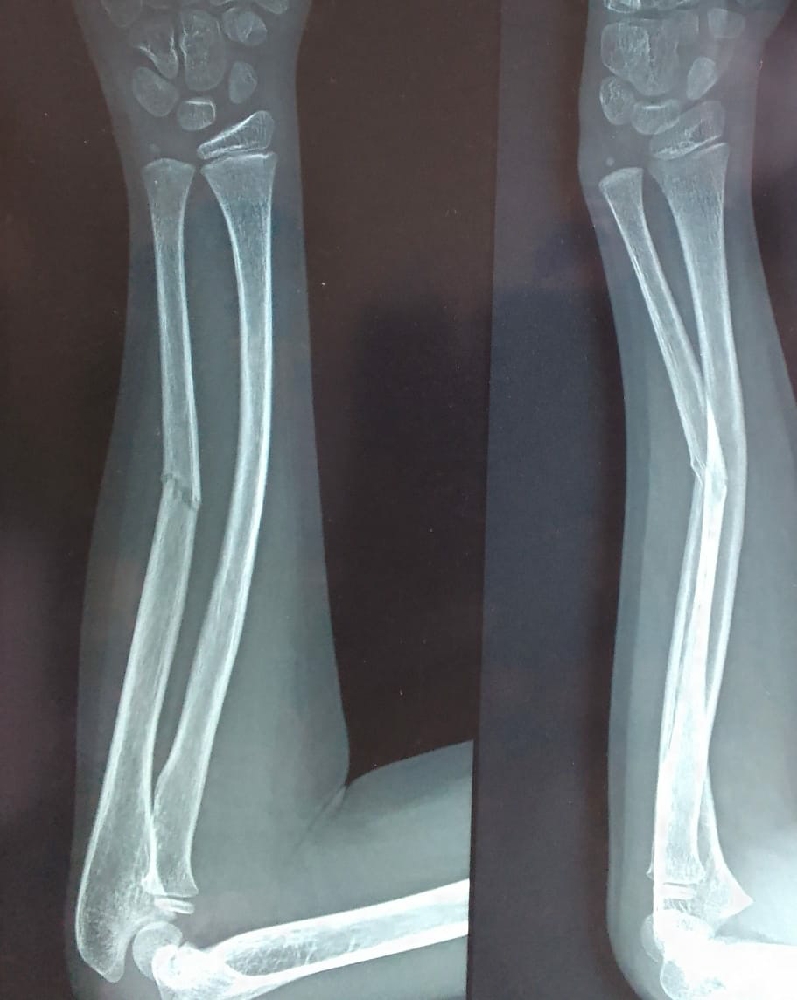

Greenstick Fracture X Ray Greenstick Fracture In Sports Web a greenstick fracture occurs when a bone bends and breaks, but doesn’t break into two separate pieces. Green stick fractures occur in arm and forearm which involves ulna, radius or humerus. Web greenstick fractures occur most commonly after a fall on an outstretched arm. Web however, if there is a fracture with a cortical breach, it is termed a. Greenstick Fracture In Sports.

Fractures Distal forearm or wrist

Green stick fracture Greenstick Fracture In Sports Web however, if there is a fracture with a cortical breach, it is termed a greenstick fracture if unicortical, or a complete fracture if. Web a greenstick fracture is a fracture in a young, soft bone in which the bone bends and breaks. Web the most common cause of a greenstick fracture is falling on an outstretched arm, especially when. Greenstick Fracture In Sports.